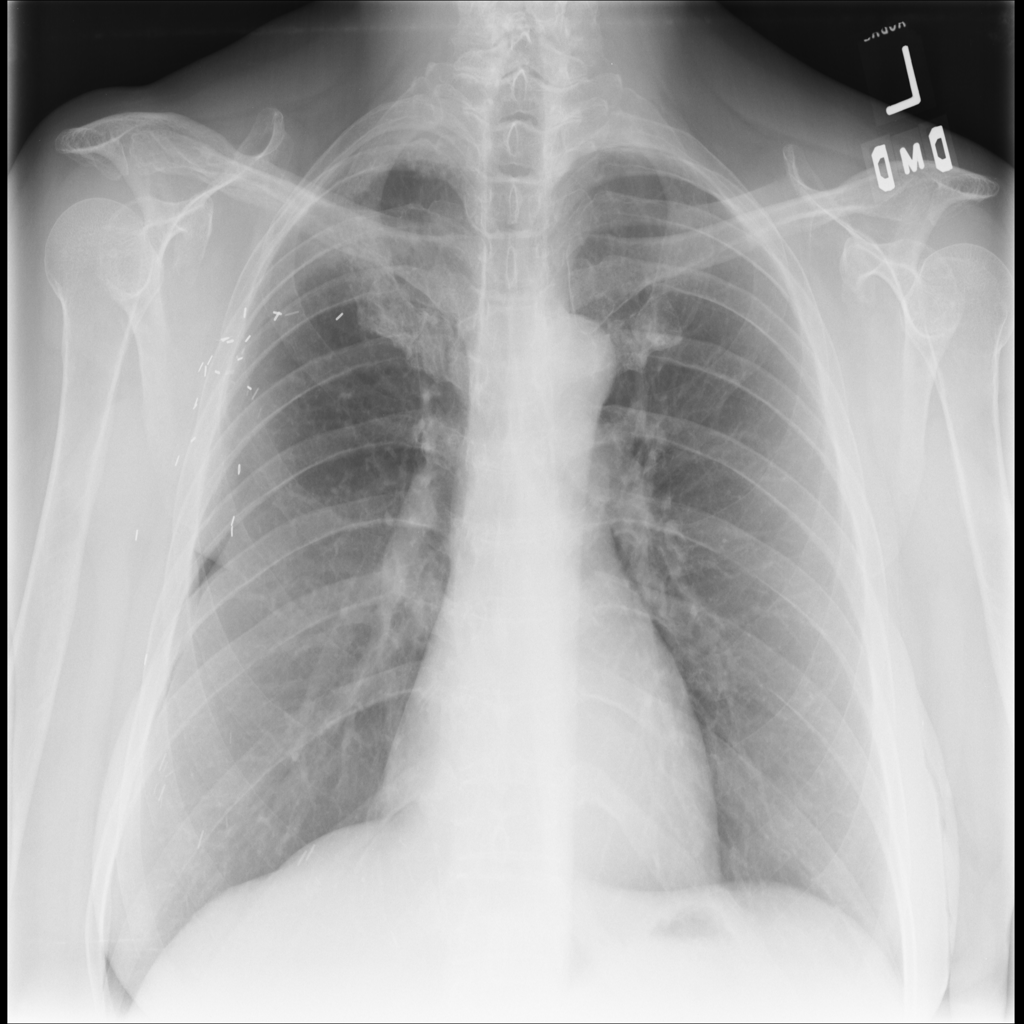

PAT-E960 · IMG-002Fibrosis

PAT-E960 · IMG-002

PA